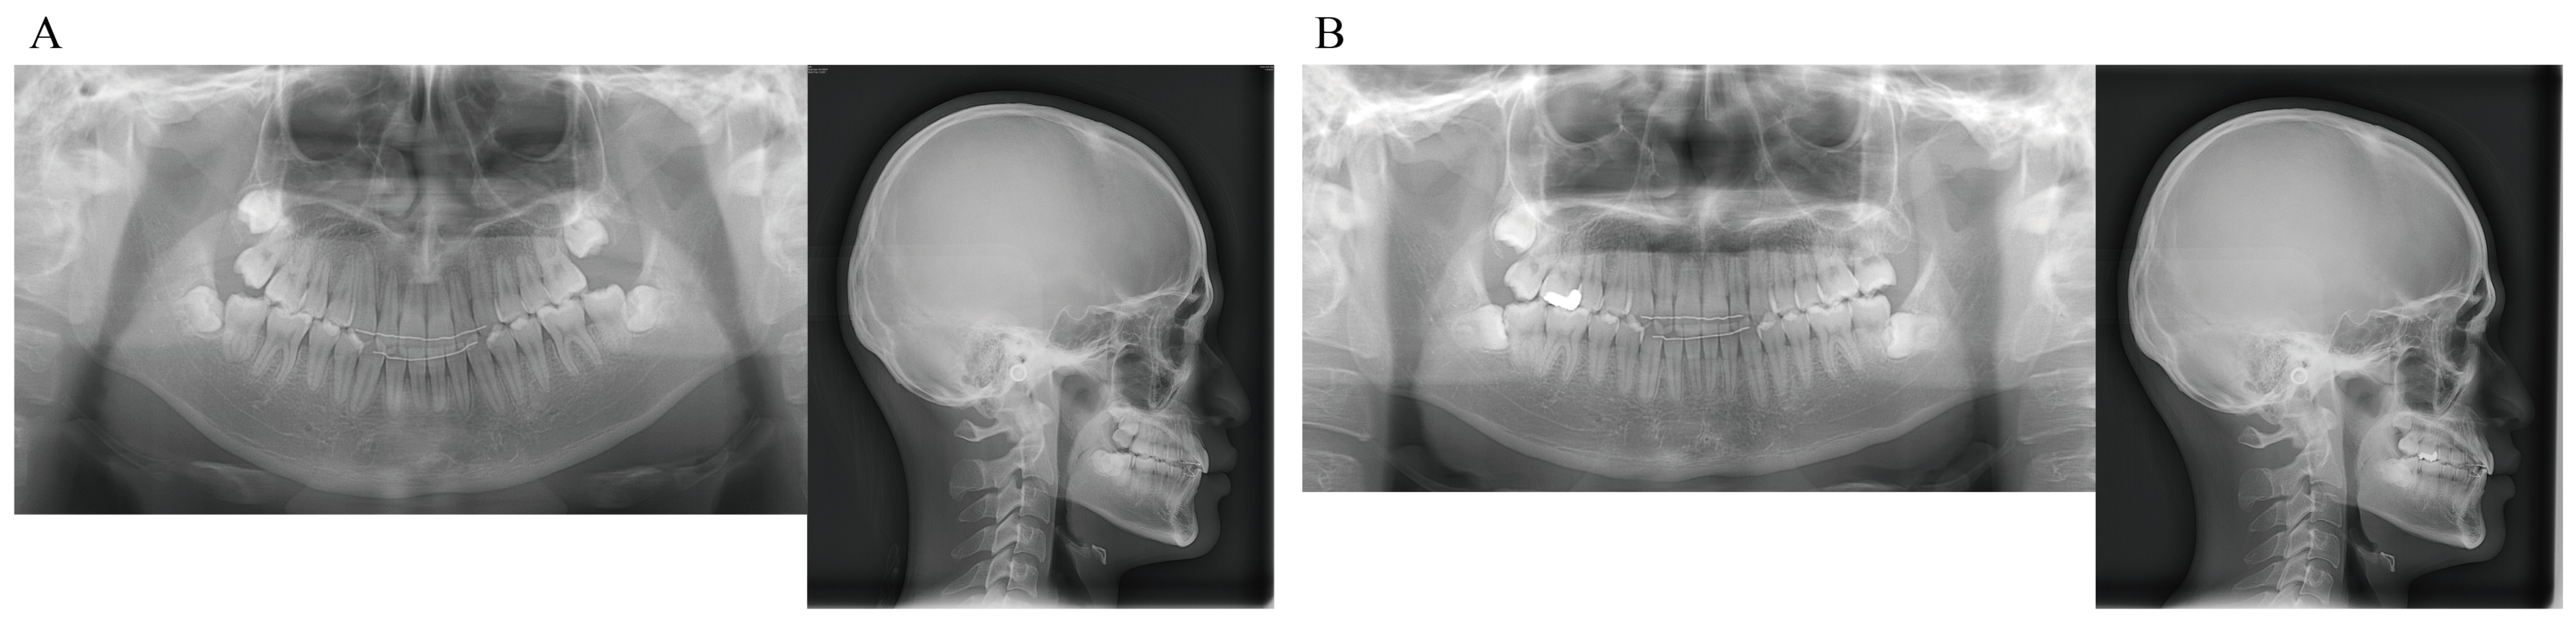

The facial features were symmetrical in the frontal view, with the maxillary midline coinciding with the facial midline and the mandibular midline deviated 1.5 mm to the right when smiling. The lateral view showed a straight profile. The occlusal relationship of the first molars was Angle Class I on the right side and Angle Class II on the left side, with overjet of +2.0 mm and overbite of +3.0 mm. The maxillary left canine was displaced to the labial side of the maxillary left lateral incisor, with its apex slightly and ectopically erupted. It was unclear whether the maxillary left deciduous tooth was lost prematurely during the deciduous-to-permanent dentition phase, as neither the patient nor his guardians could remember. Due to the mesial positioning of the maxillary left first molar, there was a lack of eruption space for the maxillary left canine, with an arch length discrepancy of −7.5 mm. The mandibular anterior teeth were slightly crowded, with an arch length discrepancy of −3.0 mm. The maxillary right lateral incisor and mandibular right lateral incisor were in crossbite (Figure 1 and Figure 2).

Panoramic X-ray and cone-beam computed tomography (CBCT) images showed that the maxillary left canine had erupted ectopically due to eruption disturbance. The maxillary left canine was mesially inclined with its crown near the labial root surface of the lateral incisor. The cusp of the canine was positioned more mesially than the lateral incisor axis. There was no evidence of canine contact with the lateral incisor or root resorption of the adjacent permanent teeth. There was no abnormality in the number of teeth. Tooth germs of the maxillary and mandibular right and left third molars were observed; the tooth germ of the maxillary left third molar was almost as large as the ipsilateral first and second molars.

Lateral cephalometric radiography showed no discordance in the anteroposterior position of the maxilla and mandible, with SNA of 90.5°, SNB of 88.5°, and ANB of 2.0°. Vertically, the patient had a low Frankfort-mandibular plane angle (FMA) of 14.0°. U-1 to NA was 2.0 mm/14.0°, indicating that the axis of the maxillary central incisor was normal, but that it was lingually positioned. L-1 to NB was 2.0 mm/14.5° and the FMIA was 80.5°, indicating that the mandibular central incisor was inclined and positioned lingually. The resulting interincisal angle was 150.0°, a large value exceeding 2SD (Figure 3).

Figure 2. Initial dental casts (age, 14 years 4 months).